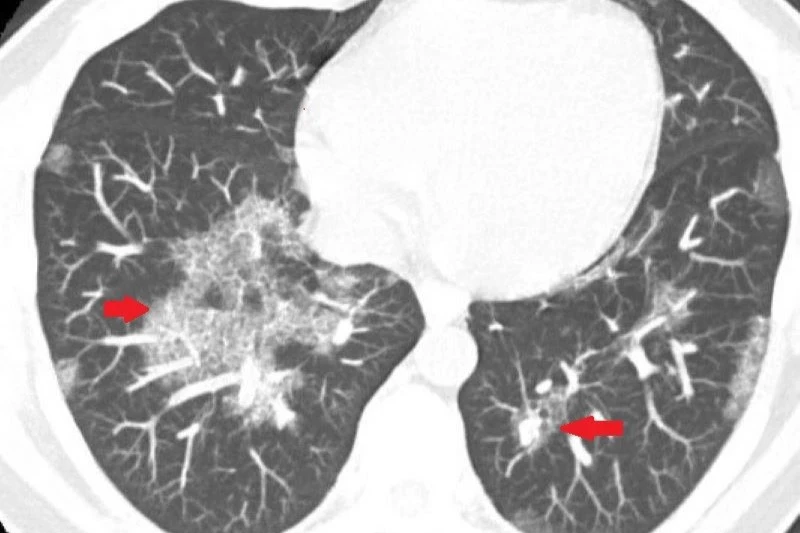

40歲魏先生近幾年感覺肺活量下降,並有間歇性暈眩與胸悶喘不過氣的狀況,甚至搬重物時感覺胸口像被壓住,近期背部劇烈疼痛,他才就醫檢查,意外發現肺部大片白影。轉診至台北慈濟醫院胸腔內科,經電腦斷層初步判斷為肺部慢性發炎,但支氣管鏡與細菌、黴菌培養檢查皆無異常,病因不明,3個月後白影惡化,再次接受肺部穿刺切片,最終確診為極為罕見的「肺部蛋白質沉積症」。

台北慈濟醫院胸腔內科主任藍冑進指出,「肺部蛋白質沉積症」(Pulmonary Alveolar Proteinosis,PAP)是一種肺泡內充滿蛋白樣物質,嚴重阻礙氧氣交換的罕見疾病。根據國外研究統計,蛋白質沉積症的發生率僅約百萬分之一,目前醫學對該病的病因仍未完全明瞭,推測與自體免疫系統異常有關。

藍冑進表示,正常情況下,肺部會分泌表面張力素等蛋白質,協助肺泡張開、促進氣體交換。但當這些蛋白質無法代謝清除,便會堵塞肺泡,導致缺氧與呼吸困難,嚴重時甚至危及生命。此病早期常無明顯症狀,易與肺炎、肺纖維化等混淆,導致誤診與延誤治療,因此提高臨床警覺性至關重要。